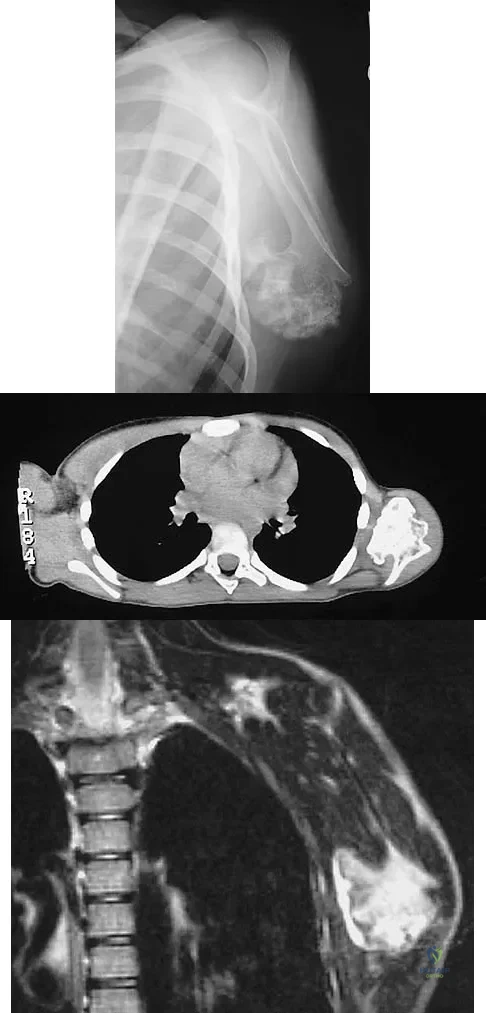

A 13-year-old patient has foot drop and lateral knee pain. AP and lateral radiographs and an MRI scan are shown in Figures 49a through 49c. A biopsy specimen is shown in Figure 49d. What is the preferred method of treatment?

Explanation